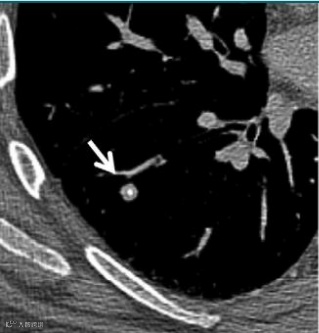

根据美国放射学会(American College of Radiology,ACR)发布的肺部 CT 筛查报告和数据系统(lung imaging reporting and data system, Lung-RADS)1.1版,肺结节可以分为以下几类:

1(阴性):

无结节和确定为良性的肺结节(含良性钙化或脂肪)。

恶性概率:小于1%

2(良性表现或良性生物学行为):

大小或直径无增长,发展为临床侵袭性肺癌的可能性低。

3(良性可能性大):

短期随访可能为良性的结节,包括侵袭性肺癌可能性低的结节。

恶性概率:1-2%

4(可疑恶性):

附加的诊断实验和/或组织标本提示。

4A:恶性概率:5~15%

4B:恶性概率:大于15%